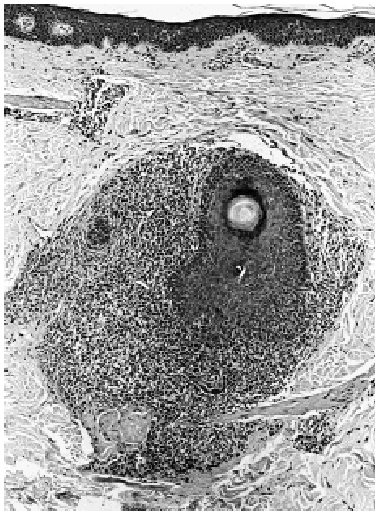

Una biopsia tomada de una de las placas de alopecia mostraba en dermis reticular un denso infiltrado linfoide atípico con células cerebriformes dispuestas exclusivamente alrededor de folículos pilosos, con permeación folicular (figs. 2, 3 y 4). En estas estructuras se advertían pequeños microabscesos, así como células atípicas aisladas con halos perinucleares. No existía mucinosis folicular y la epidermis suprayacente no mostraba epidermotropismo. El estudio inmunohistoquímico fue intensamente positivo para CD3, CD43 y negativo para CD79 alfa y CD20. Una biopsia de la adenopatía inguinal demostró infiltración ganglionar específica por linfoma cutáneo.

Fig. 3.--Detalle de la infiltración linfoide perifolicular (hematoxilina-eosina).